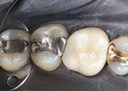

Kyle Chock #15 caries removal